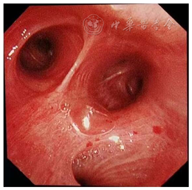

患者,男,56岁,因发热、咳嗽、咳痰伴活动后胸闷3 d于2019年9月10日入院。患者3 d前无诱因出现发热,体温在38 ℃左右,无畏寒、寒战,无盗汗,发热无明显规律性,伴咳嗽,咳少许黄白痰,无胸痛、咯血,伴胸闷、憋气,活动后加重,无消瘦,无头晕、恶心、呕吐,门诊行胸部CT考虑双肺感染性病变,为进一步诊治收住院。患者入院的20 d前在日本出差时出现咽痛,自服感冒药物(具体不详)后好转。既往有“冠心病、高血压”病史4年,2015年行冠脉造影示冠状动脉肌桥,无吸烟史,无禽类、粉尘、工业毒物接触史。体格检查:体温36.5 ℃,脉搏84次/min,呼吸23次/min,血压137/75 mmHg(1 mmHg=0.133 kPa),神志清,全身皮肤无皮疹,口唇发绀,双肺呼吸音粗,双下肺可闻及湿性啰音,心率84次/min,律齐,未闻及杂音。腹软,无压痛、反跳痛,双下肢无浮肿,四肢肌力正常。入院后查动脉血气分析(未吸氧):pH为7.374,二氧化碳分压为39.4 mmHg,氧分压为52.6 mmHg,血氧饱和度为84.8%,乳酸为1.1 mmol/L;血常规:白细胞计数为7.68×109/L,中性粒细胞百分比为 72.1%,淋巴细胞百分比为17.2%,红细胞计数为4.47×1012/L,血沉为16 mm/h;血生化:白蛋白为36.3 g/L,葡萄糖为6.44 mmol/L,乳酸脱氢酶为284 U/L,C反应蛋白为30.9 mg/L,三酰甘油为2.25 mmol/L;血凝常规:纤维蛋白原含量为4.67 g/L;肺肿瘤标志物CYFRA21-1为11.3 ng/ml;降钙素原为0.052 μg/L;病原学检查:半乳甘露聚糖试验(GM试验)为0.38 μg/L;痰细菌培养、真菌涂片、结核菌涂片阴性;肺炎支原体抗体、衣原体抗体、呼吸道合胞病毒抗体、出血热病毒抗体、真菌葡聚糖、巨细胞病毒核酸检测均阴性;免疫相关:抗核抗体(ANA)、抗环瓜氨酸肽抗体(CCP)、抗中性粒细胞胞浆抗体(ANCA)均阴性;机体细胞免疫评价正常;尿常规、大便常规、肌钙蛋白、脑钠肽均正常;乙肝表明抗原、丙肝抗体、梅毒抗体、HIV抗体均阴性;心电图示窦性心律、心电轴中度左偏、ST-T异常;胸部CT考虑双肺感染,建议治疗后复查,心影饱满,冠脉钙化,两侧胸膜略增厚(图1A~C)。入院后给予经鼻高流量湿化氧疗(氧浓度50.0%,氧流量50 L/min),美洛西林舒巴坦(2.5 g,1次/12 h)联合左氧氟沙星(0.6 g,1次/d)抗感染,奥司他韦胶囊(75.0 mg,2次/d)抗病毒,多索茶碱(0.3 g,1次/d)扩张支气管,溴己新(4.0 mg,2次/d)止咳化痰,低分子肝素钠(5 000 U,ih,1次/d)抗凝,硝苯地平缓释片(10.0 mg,2次/d)降压治疗,患者体温逐渐降为正常,但活动时胸闷无改善,经皮血氧饱和度在95.0% 左右(上述氧疗情况下),考虑抗感染解痉平喘治疗效果不佳,不除外间质性肺病,遂于9月14日加用甲泼尼龙(40.0 mg,1次/12 h)静滴,自觉症状略有好转,于9月17日复查胸部CT示双肺片状影较前增多(图2A~C),提示疾病进展,与患者及家属沟通后于9月17日行床旁支气管镜检查,镜下见左右肺各叶段支气管通畅,黏膜轻度充血,可见少量白色泡沫样分泌物,未见狭窄、出血及新生物(图3),于右肺下叶后基底段行肺泡灌洗及透壁肺活检,肺泡灌洗液(BALF)细胞分类示淋巴细胞百分比为63.0%,中性粒细胞百分比为24.0%,巨噬细胞百分比为8.0%,上皮细胞百分比为5.0%;BALF细菌、真菌涂片和培养均阴性;BALF结核菌涂片、结核菌核酸扩增检测(Gene Xpert)均阴性;BALF脱落细胞学检查阴性;BALF-GM试验0.55 ng/ml;BALF病原微生物宏基因组检测(NGS)示产黑色素普雷沃菌(序列数12)、龋齿罗氏菌(序列数7)、简明弯曲杆菌(序列数1);支气管镜肺活检病理考虑肺间质纤维化(图4)。患者对治疗反应不佳,为排除肿瘤于9月20日行正电子发射计算机断层显像(PET-CT)示双肺多发斑片影、结节灶,大部分见支气管充气征,部分结节边缘见分叶和毛刺,SUVmax 6.4,考虑感染性疾病,霉菌感染可能性大,肉芽肿性炎和MALT淋巴瘤不除外(图5)。请北京协和医院专家会诊,考虑ILD,不除外结缔组织病相关,建议加大甲泼尼龙(80.0 mg,1次/8 h)用量,升级抗生素为美罗培南(1.0 g,1次/8 h),完善肌炎谱13项示抗Jo-1抗体阳性,最终诊断为抗Jo-1抗体综合征,加用环磷酰胺(0.4 g,1次/周)静滴8次,并逐渐减少甲泼尼龙用量,患者胸闷症状明显好转,2019年11月18日复查胸部CT示肺内病变较前明显吸收好转(图6A~C),随访1年,病情稳定。